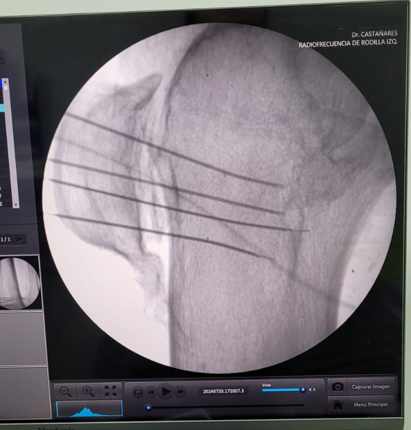

En Tidol tratamos el caso de un paciente de 90 años, con artrosis severa de rodilla izquierda.

El paciente presentaba limitaciones de reemplazo total de rodilla y no se le podía realizar la cirugía por osteoporosis y comorbilidad; por lo que se decidió realizar tratamiento con radiofrecuencia de los nervios geniculados.

Previo al tratamiento, el paciente no podía caminar debido a dolor; luego del tratamiento mejoró notablemente su sintomatología, comenzando a realizar la rehabilitación con fisioterapia dirigida.